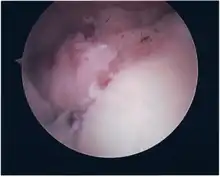

Repair of SLAP Tear

• The glenoid and labrum are roughened to increase contact surface area and promote re-growth.

• Locations for the bone anchors are selected based on number and severity of tear. A severe tear involving both SLAP and Bankart lesions may require seven anchors. Simple tears may only require one.

• The glenoid is drilled for the anchor implantation.

• Anchors are inserted in the glenoid.

• The suture component of the implant is tied through the labrum and knotted such that the labrum is in tight contact with the glenoid surface.